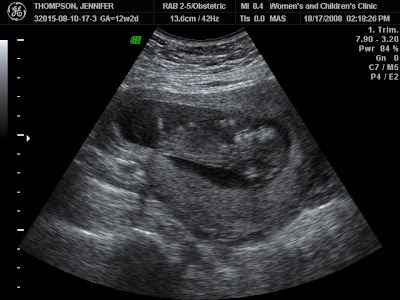

Baby Thompson's First Photo!

We had our first ultrasound on Friday! We were 12 weeks at the time of these pictures, still to early to detect the sex of the baby! But according to the tech there appears to be just 1 bun in this oven! So if you voted for twins it looks like that isn't the case this time. Unless the other one was just hiding. :) It's always fun to get to see the baby! I asked Zach when we left the doctor if he felt like it was a boy or a girl...he said boy...even though prior to the ultra sound he thought it was going to be a girl! He said "the ultrasound looked just like the other two and they were both boys." Now we have to remember that Zach didn't go to school to read sonograms. haha...we told the tech we already have 2 boys & she commented that this one's nose looked like a little girl! I am sure she was just saying that to keep our hopes up! haha...We would be just fine with another little Zach! We would almost have our our starting line up! :) What do you think by looking at the pictures? Does you vote change?